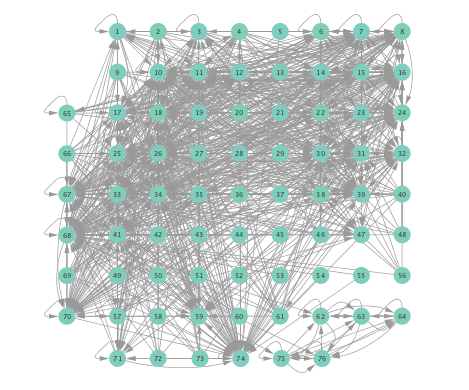

Figure 2 depicts networks inferred from different algorithms for both preictal and ictal intervals of the time series. The figure illustrates results obtained by the linear SVARM, and the K-SVARM approach with and without kernel selection. Each node in the network is representative of an electrode, and it is depicted as a circle, while the node arrangement is forced to remain consistent across the four visual representations. A cursory inspection of the visual maps reveals significant variations in connectivity patterns between ictal and preictal intervals for both models. Specifically, networks inferred via the K-SVARMs, reveal a global decrease in the number of links emanating from each node, while those inferred via the linear model depict increases and decreases in links connected to different nodes. Interestingly, the K-SVARM with kernel selection recovered most of the edges inferred by the linear and the K-SVARM using a polynomial kernel, which implies that both linear and nonlinear interactions may exist in brain networks. Clearly, one is unlikely to gain much insight only by visual inspection of the network topologies. To further analyze differences between inferred networks from both models, and to assess the potential benefits gained by adopting the novel scheme, several network topology metrics are computed and compared in the next subsection.